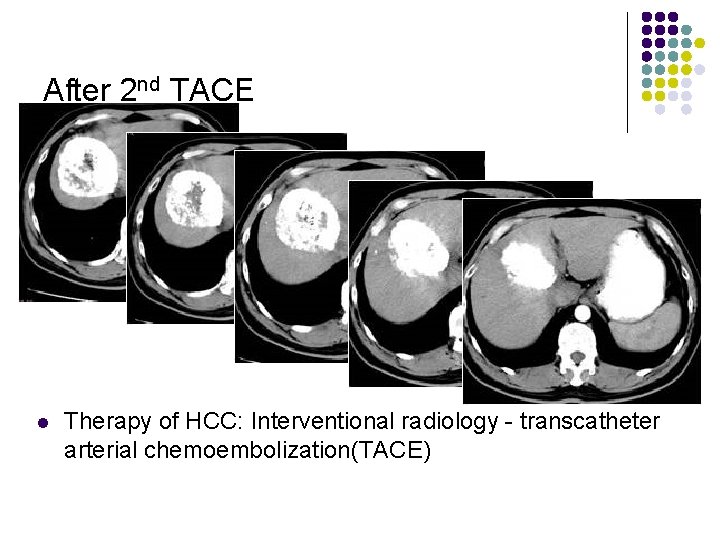

After 2 nd TACE l Therapy of HCC: Interventional radiology - transcatheter arterial chemoembolization(TACE)